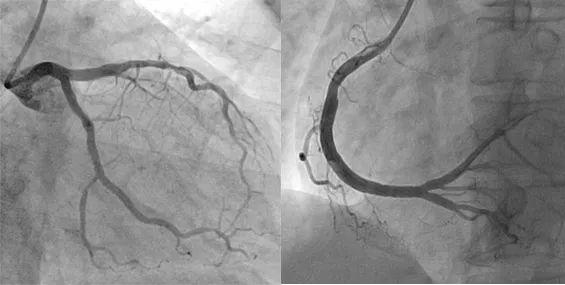

冠脉造影正常咋还有心绞痛了呢?